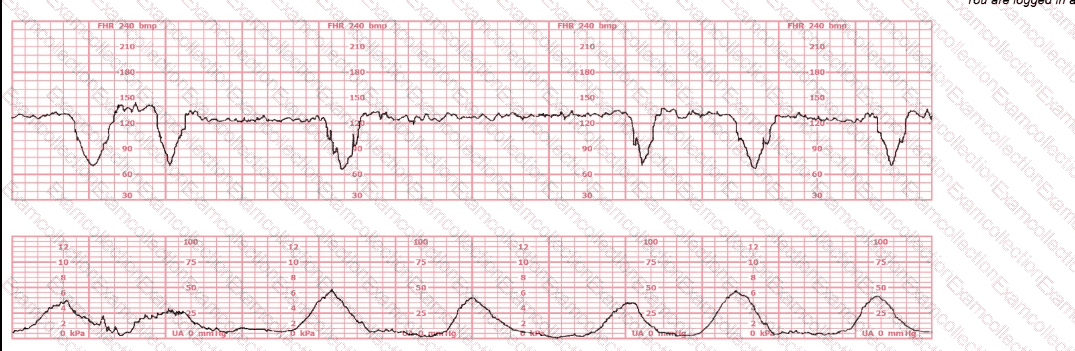

A woman is being induced with oxytocin. The tracing shown is representative of 20 minutes. Based on this tracing, the next step would be to: